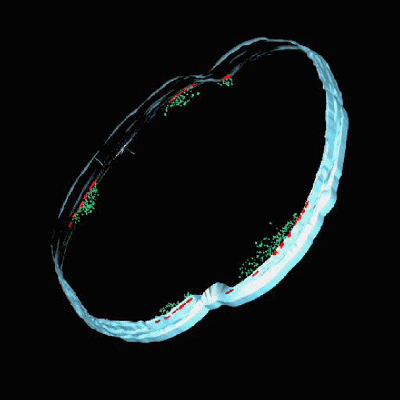

登录/注册后可看大图

FMMs的模拟图,那些红红绿绿的就是

有FMMs的时候,PBP2a并列在一起,耐青霉素;

FMMs被破坏之后,PBP2a不能聚合,MRSA又对青霉素敏感